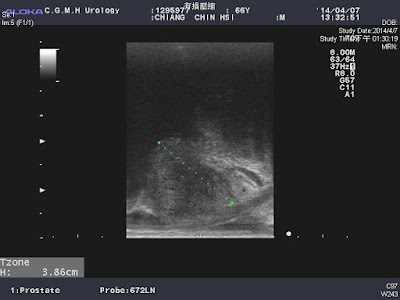

因為有上一次的手術經驗,江先生想先做一次膀胱泌尿內視鏡看看是否有阻塞,下圖為軟式膀胱鏡的圖形,右側黑黑的是如同胃鏡一般的膀胱鏡,整個轉頭回來就可以看膀胱的出口,有一顆大貢丸般地將膀胱出口阻塞(遠遠大於前列腺超音波中所呈現的大小)~~~看到這個"大貢丸",江先生就決定接受前列腺雷射剜除手術,解決困擾